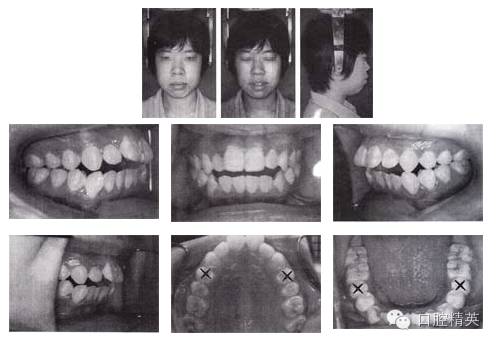

圖3-1 矯治前面像及口內(nèi)像(開始矯治 2002-08-25)

檢查:恒牙列,雙側(cè)磨牙中性偏遠(yuǎn)中關(guān)系,11、12 、13 、21、22 、23中度開頜,上下頜牙列輕度擁擠。正面觀,面型左右對(duì)稱;側(cè)面觀,雙頜前突,明顯開唇露齒,下頜頦部發(fā)育不良致后縮。顳下頜關(guān)節(jié)無(wú)異常。

1.拔牙矯治,拔除14、24、35、45和38、48